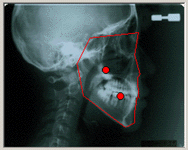

検査結果の説明

検査の結果から、具体的にどんな装置をつけるのか、期間はどのくらいになるのか、抜歯は必要かどうか、治療費はいくらかかるかなどを説明します。